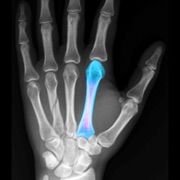

BoneGauge allows you to approximate an individual's bone density and quality from a mobile platform. BoneGauge helps you make measurements of cortical thickness of the second metacarpal from either hand or wrist x-rays. Use your smart phone camera to take a photo of the second metacarpal on an x-ray, or make measurements from an image saved in your photo library.

BoneGauge accurately calculates 2nd metacarpal cortical percentage (2MCP) in a semi-automated fashion. 2MCP has been shown to correlate with hip bone mineral density and T scores from DXA scans. Measurements made in the app will be uploaded to a central database. When combined with a patient's age, gender, and DXA score, past measurements will also help the improve the accuracy of future measurements.

This app allows you to estimate an individual's global T score in an office or hospital setting, by simply taking a photo of the 2nd metacarpal. While this measurement may not completely replace DXA, it may help a clinician screen a patient's bone quality to assist in treatment decisions and determine who may benefit from further bone density testing or osteoporosis treatment.

• Screenshot #2 pour BoneGauge